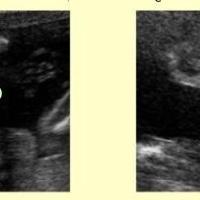

Dalla 9° alla 11° settimana: finisce il periodo embrionale ed inizia quello fetale. Gli occhi si chiudono, l’ernia addominale rientra e le cellule del sangue iniziano a essere prodotte dal fegato;

12° settimana: si differenziano i genitali esterni ed iniziano i primi movimenti fetali data l’acquisizione del tono muscolare. La milza e non più il fegato produce le cellule del sangue.